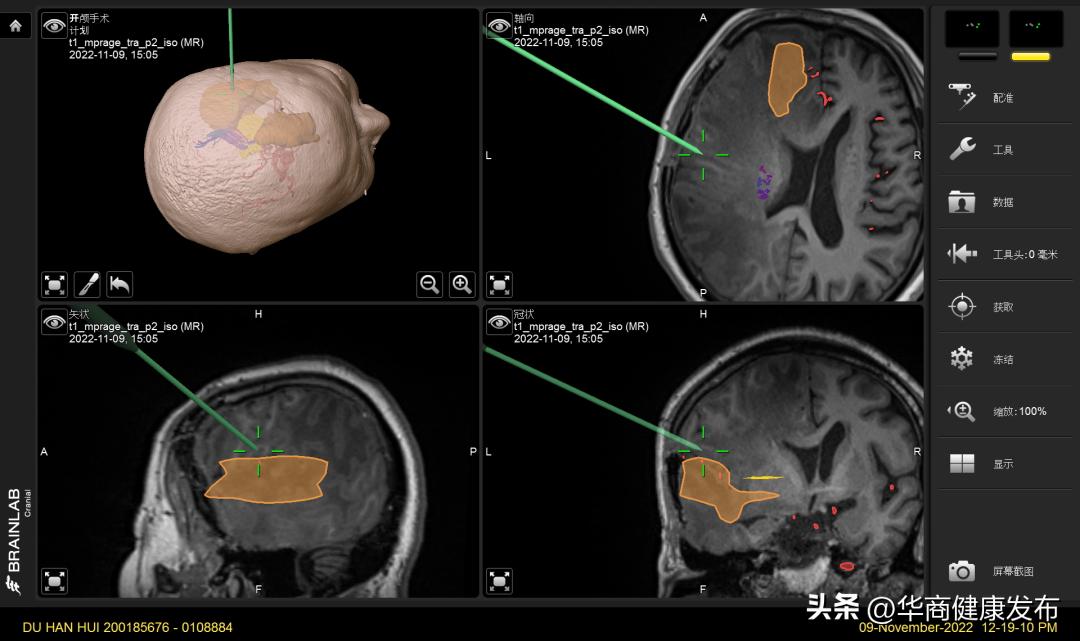

初步考虑患者系复发多发恶性颅内肿瘤,为延长生存周期,改善目前生存质量,需尽快再次手术。两个不同部位的巨大肿瘤,如何一次手术切除?又如何能做到切除 “精准、干净、无并发症”?面对这一难题,脑科医院贺世明副院长主持术前讨论会,麻醉手术中心、影像诊疗中心等多学科多位专家进行了认真讨论,制定了详细的手术计划,拟采用最新的术中核磁共振扫描、术中导航系统进行手术;对术前多模态影像融合建模。为确保万无一失,他们制定严谨的术前计划、风险预案,组织多次术前术中配合演练,使每一位工作人员熟悉掌握手术流程,力争做到手术操作和术中转运、扫描检查流畅无缝链接。患者常年生病,家庭经济状况很差,高亚飞副主任医师主动向捷裕昌慈善基金申请救助,解决了本次治疗的费用问题。

手术如期顺利展开。贺世明副院长和高亚飞副主任医师走上手术台,先用神经导航定位系统对肿瘤精确定位,确定最精准最微创的手术切口。紧接着,医生切开头皮,打开部分颅骨,暴露脑膜。为了确保手术的精准,再次导航确认肿瘤部位无误,看似普通的笔状神经导航棒在头上再次轻点,竟然能神奇的看穿颅内的一切,包括肿瘤的位置、形状及和周围功能区神经纤维束的关系。

在导航引导下找到肿瘤后,贺世明副院长在手术显微镜下连续切除两个部位的颅内肿瘤。为了确保肿瘤最大化安全清除,降低复发的风险,高端的术中3.0T核磁登场,因为此时患者的头颅成打开状态,为避免感染、无菌尤为重要,先简单覆盖脑膜和头皮,再用大纱布固定,每一步都严格无菌操作,里三层外八层的将患者包裹至“粽子状”,再将核磁转运床推至手术间和手术床对接,把患者安全平滑转运至核磁检查室。由于核磁检查室不能有任何带磁性的金属进入,否则会造成灾难性后果,所以室内一定要使用术中核磁专用的磁兼容监护仪和麻醉呼吸机。约30分钟,核磁检查完毕,将患者再次转运至手术间,依次暴露伤口,再次消毒,无菌操作依旧非常重要,这直接关系这位患者的术后恢复,甚至生命安全。

刚刚扫描出来的核磁影像数据自动传输至导航系统,医生轻点一键,术中影像和术前影像瞬间自动融合在一起,一颗完美无瘤的大脑成像便展示在我们眼前。医生随即依次缝合各层组织,手术顺利结束。